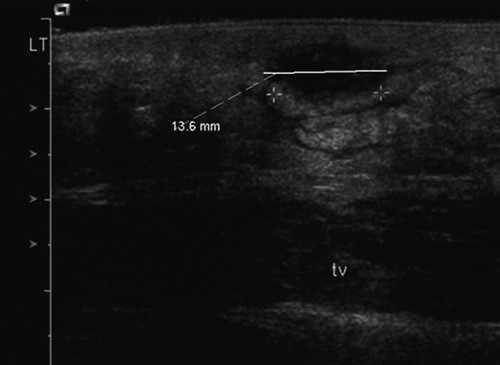

Ultralyd abdomen viste en 6 x 10 x 10 mm stor væskeholdig abscess i hudnivå, uten kommunikasjon med dypere lag eller fri bukhule (fig 2). Denne ble åpnet ved punksjon, og 0,5 ml purulent abscessinnhold ble sendt til gramfarging og mikroskopi samt dyrking. En gynekologisk undersøkelse avdekket normale forhold i vagina, portio og vulva. Ingen tampong ble funnet.